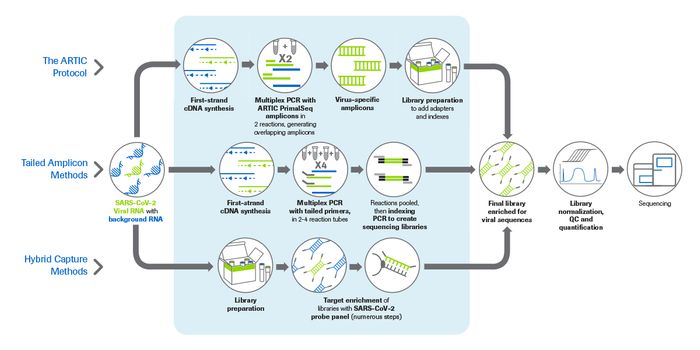

MAY 18, 2021Genetics & GenomicsAs the SARS-CoV-2 virus continues to mutate, rapid sequencing of COVID-19-positive samples is more critical than ever. N ...